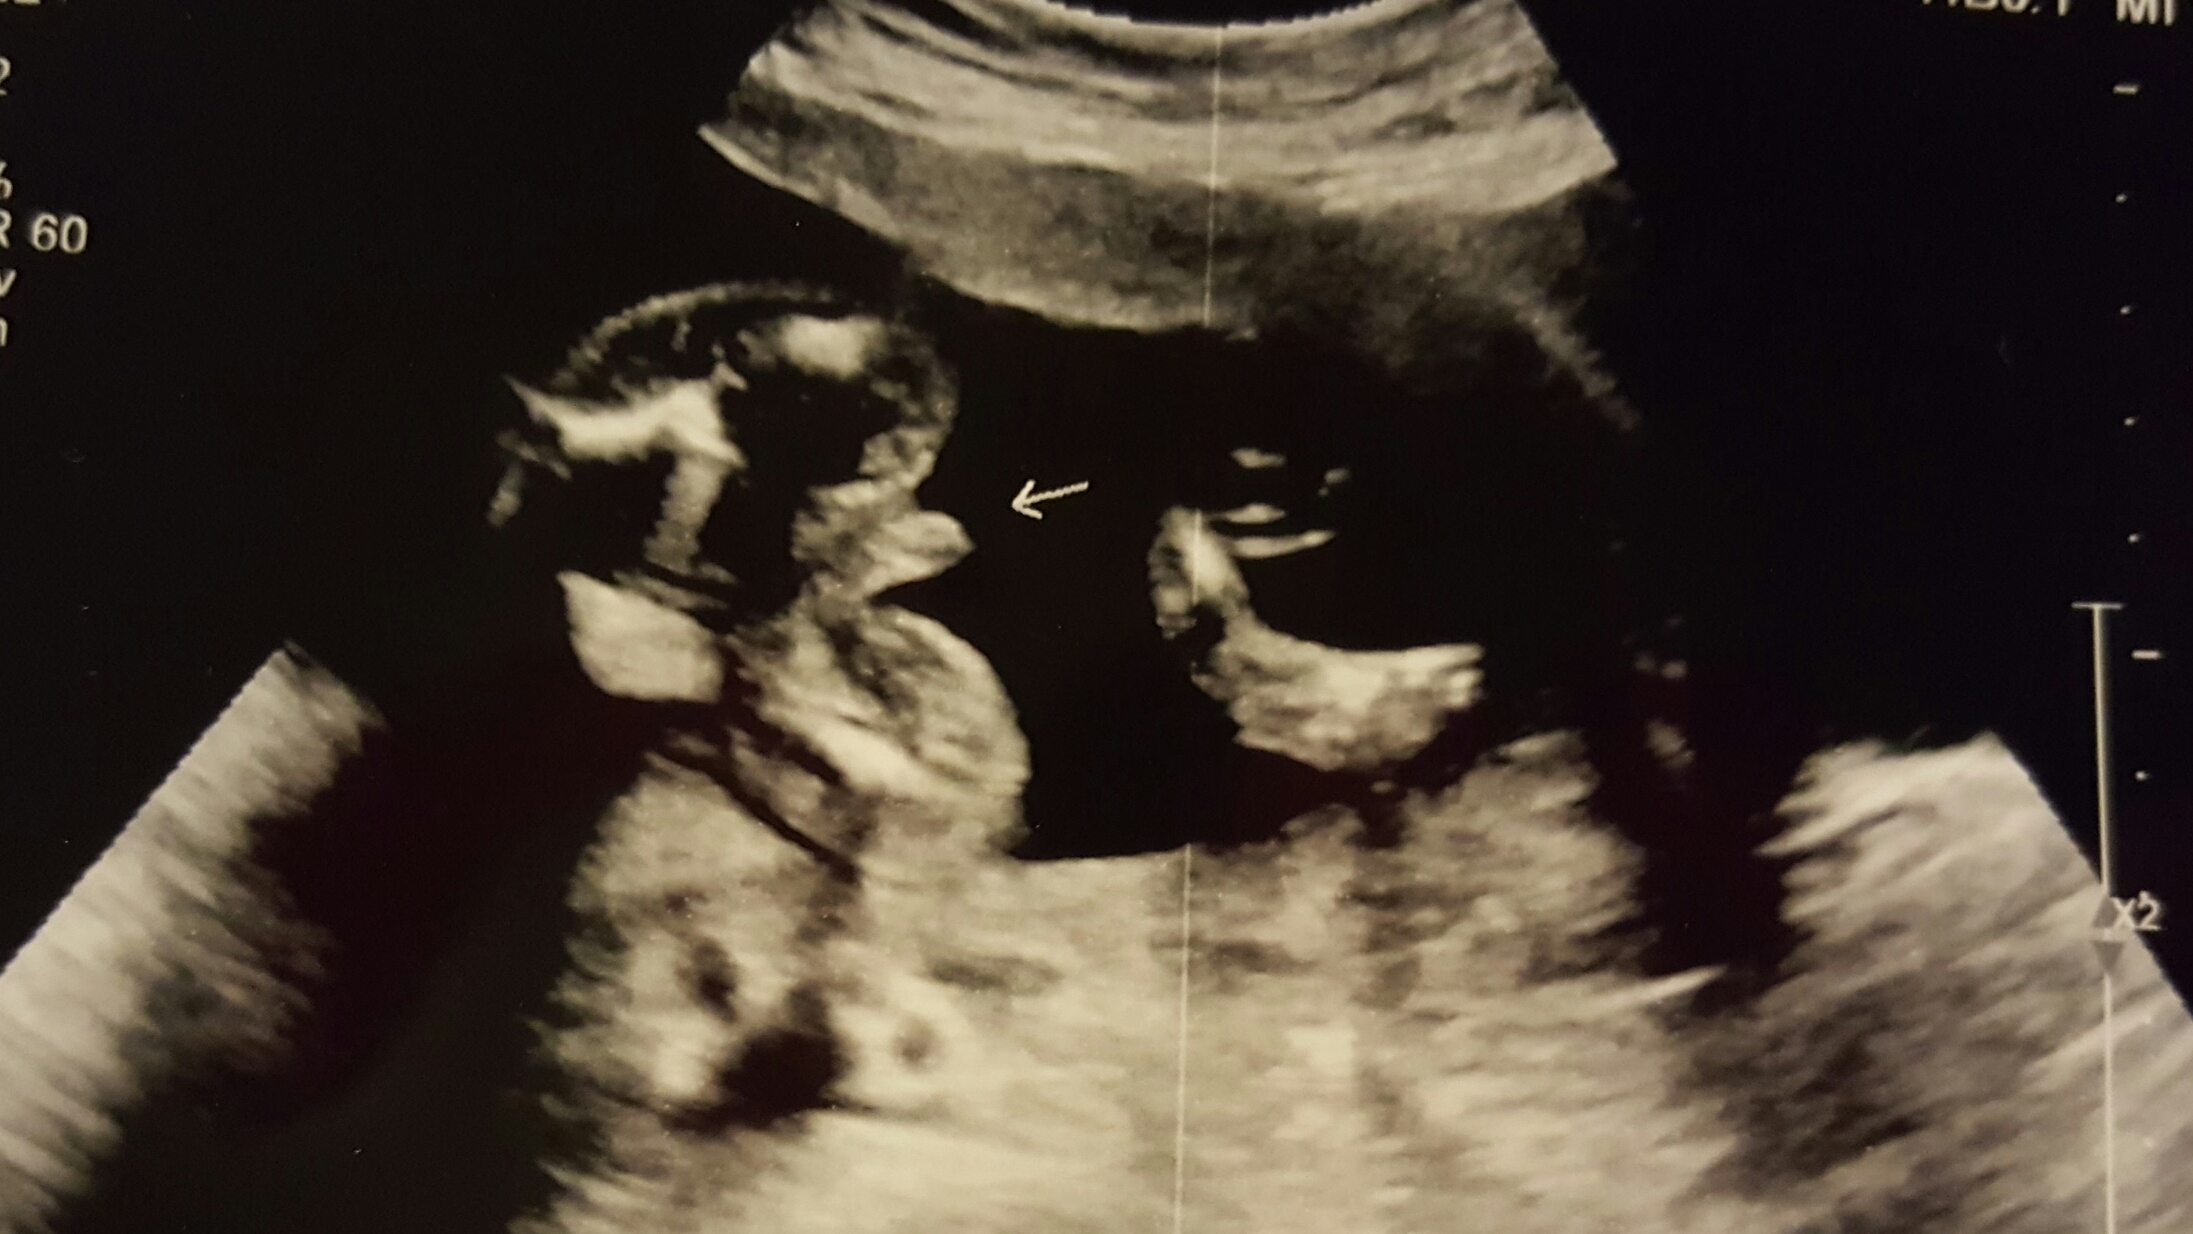

Boy?

I have a boy already but this pregnancy has been so different as I have been sick, I'm not showing still and a few other things it just keeps making me think it's a girl but these ultrasounds are pretty close to looking like my first! And the tech couldn't see for awhile as baby had his legs crossed then the umbilical cord was in the way so now I'm freaked out that it could be a mistake! What do you think!? Thanks ladies!Attachment 34294Attachment 34295

Boy! I just had my 14 week ultrasound & it looks like this & they also said boy. I also still have vomiting/nausea in the mornings! Ive been a lot more sick this pregnancy with my boy more than i was with my 2 girls. Congrats!!!